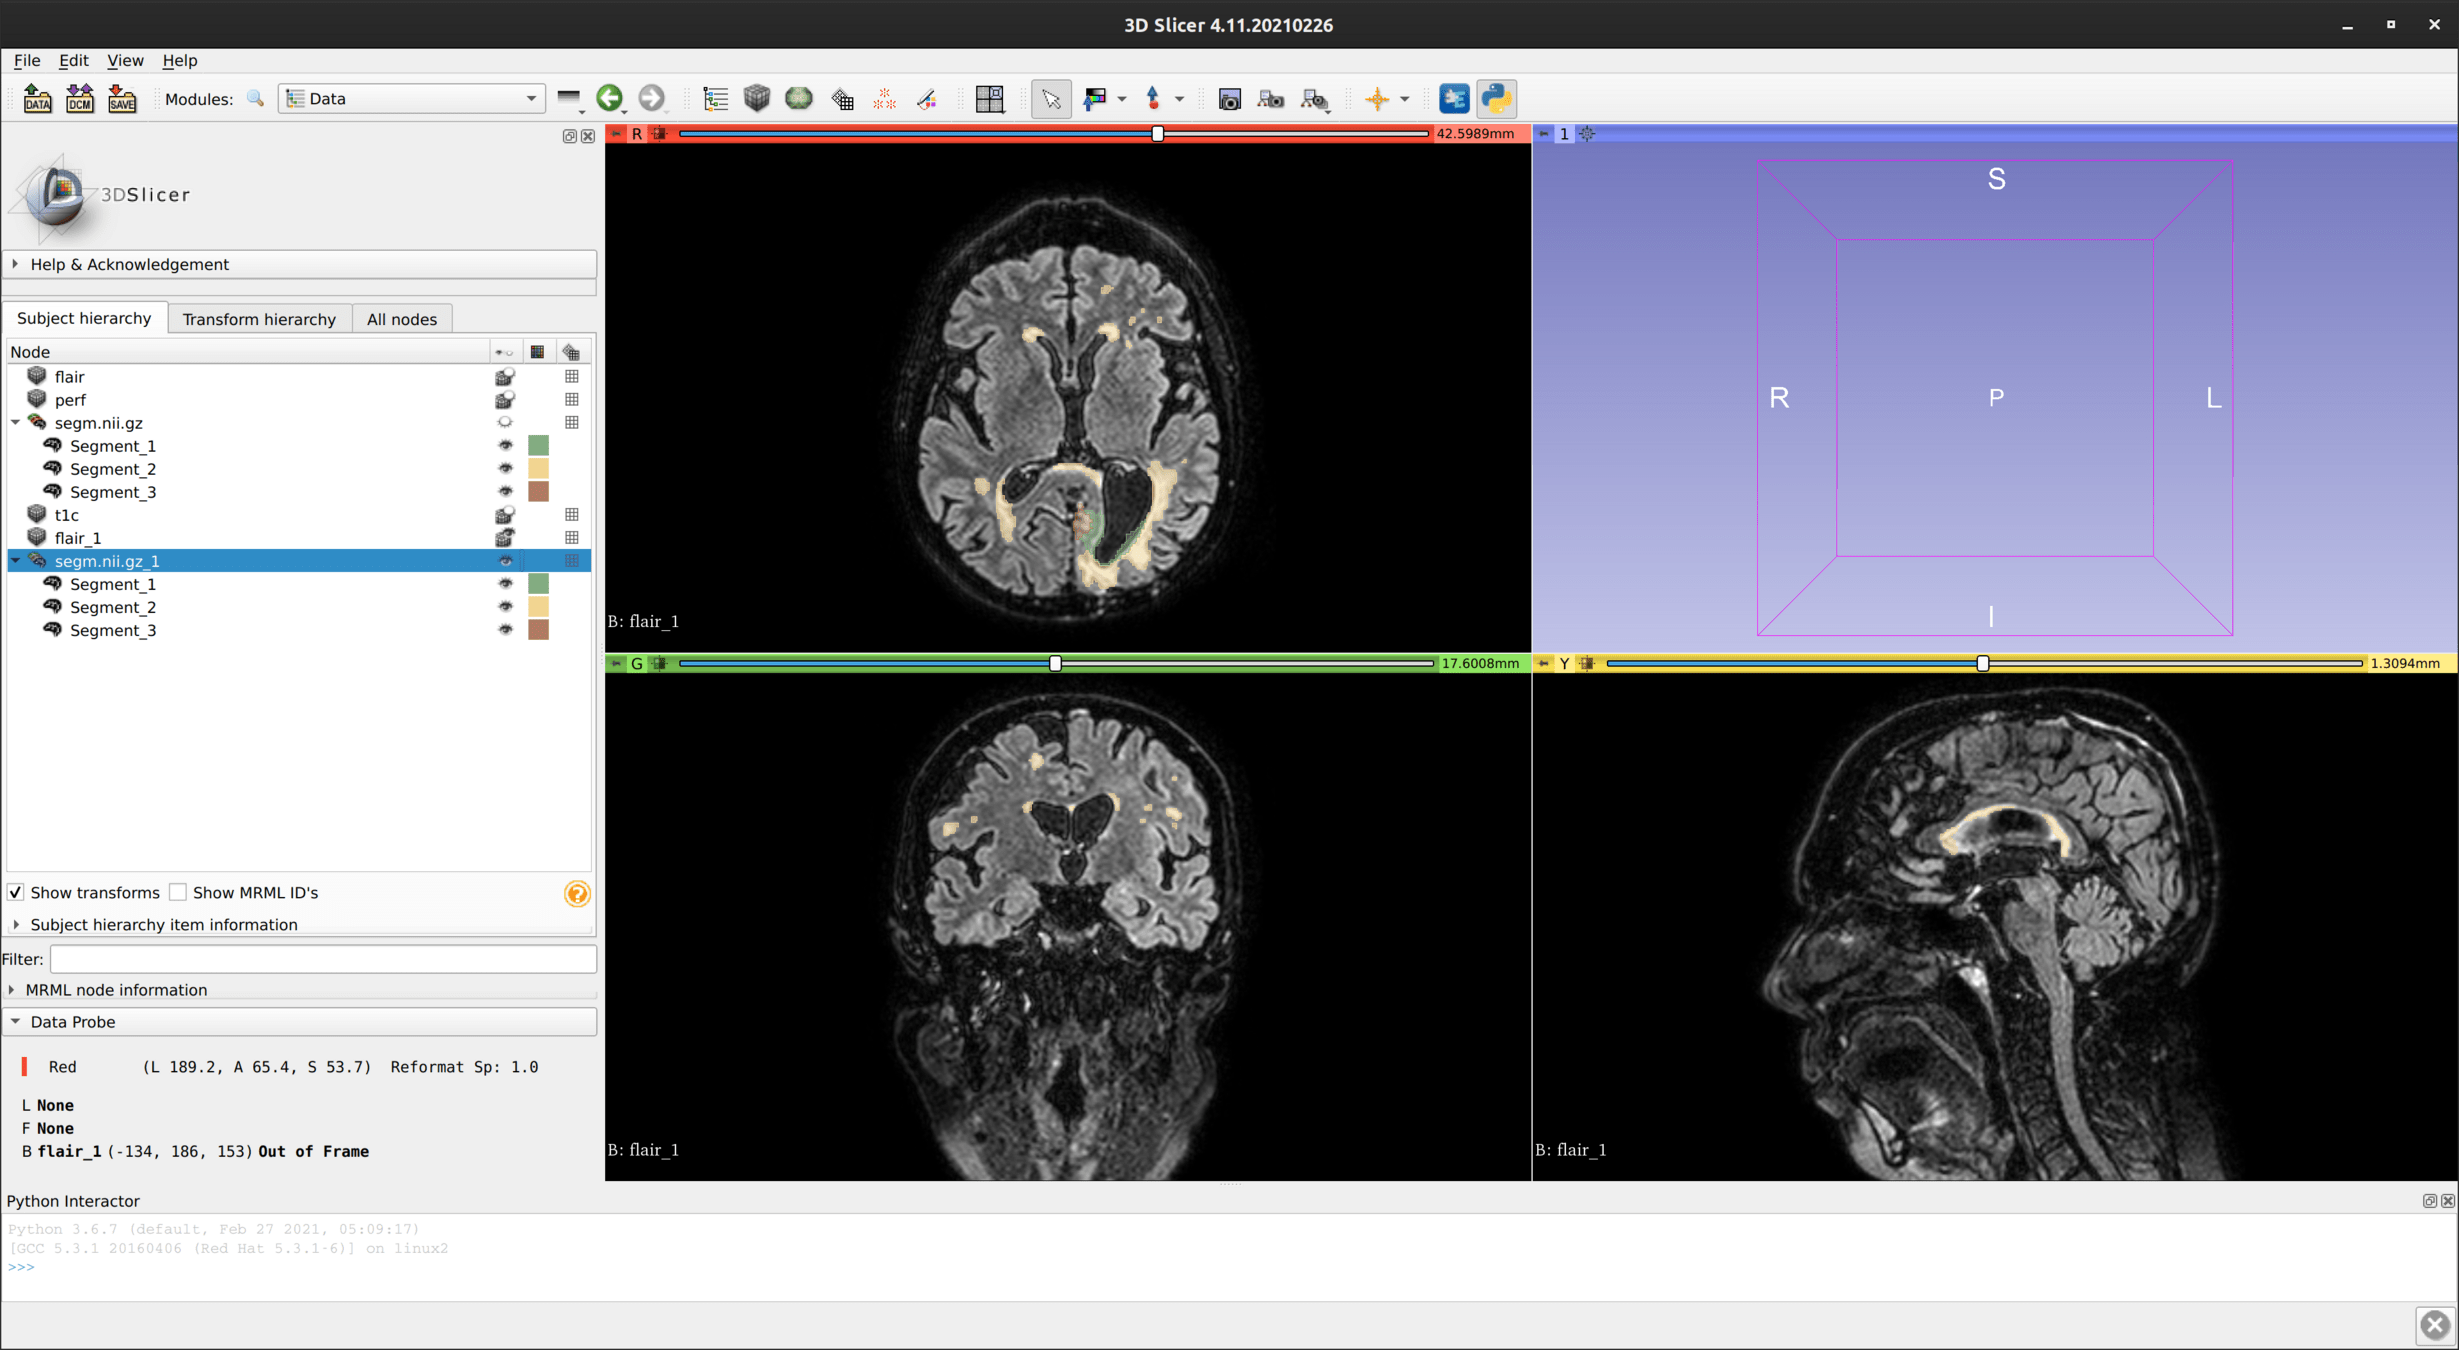

Patient 58

t=

9

14

19

23

36